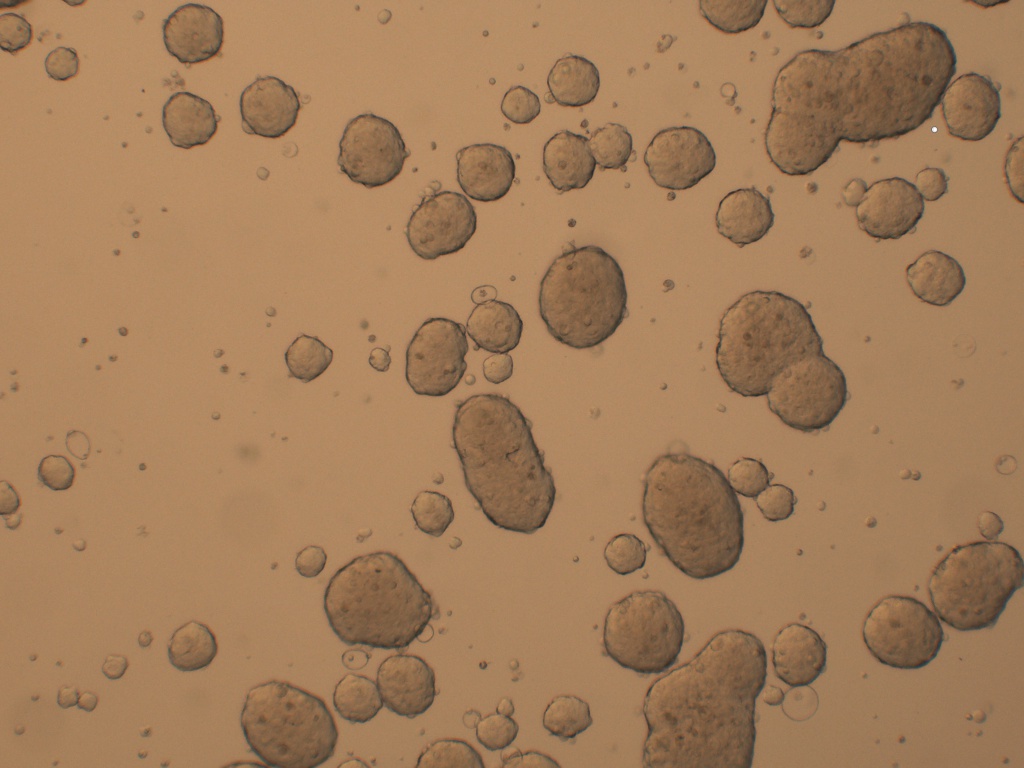

产品介绍 Cancer Stem cells Spheres Medium(肿瘤干细胞成球培养基)是一款用于将癌症干细胞(CSC)培养成3D球的培养基。癌症干细胞(CSC)被定义为肿瘤内的一小部分细胞,具有自我更新的能力,并且经常在化学疗法治疗后驱动肿瘤的进展和复发。因此,针对CSC的特定疗法的开发有望改善癌症患者的生存和生活质量,特别是对于患有转移性疾病的患者。

肿瘤干细胞成球培养基是一种新的化学成分确定和无血清的癌症干细胞培养基,可支持CSC形成3D球状细胞的聚集和扩增。

7、 4-10 天左右在超低吸附板孔中央区域会形成肿瘤球体;